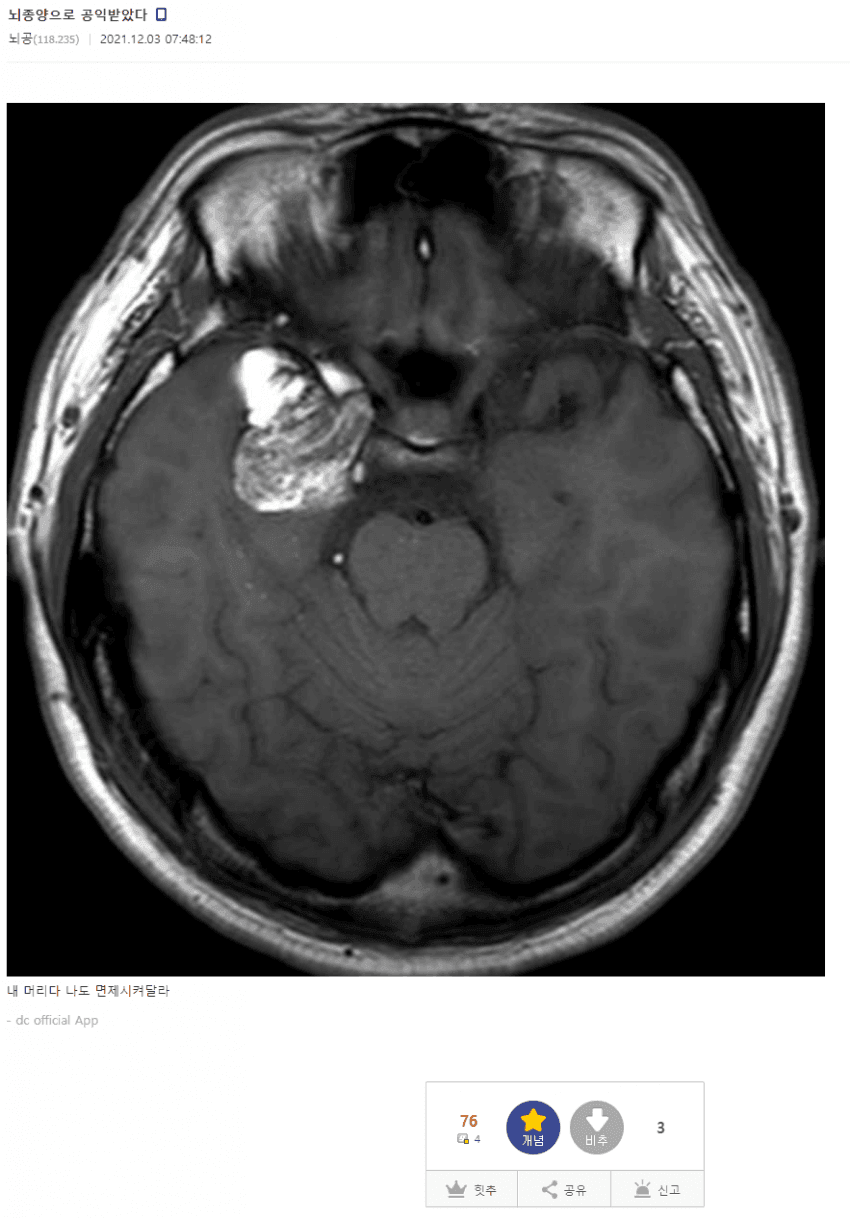

¿À½Ï¿À½Ï ³úÁ¾¾ç °øÀÍ.jpg